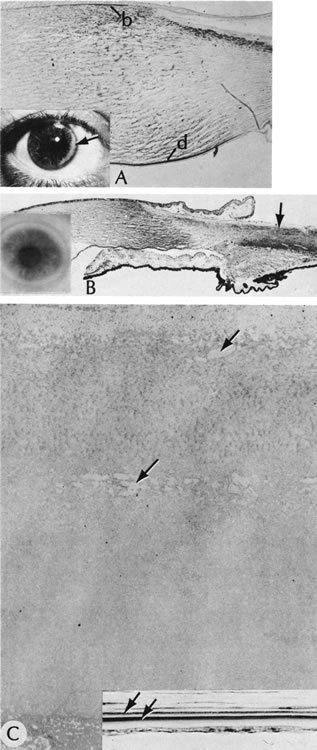

77. Waring GO3rd , Rodrigues MM: Ultrastructure and successful keratoplasty

of sclerocornea in Mietens' syndrome. Am J Opthalmol 90:469, 1980.

78. Kim T, Cohen EJ, Schnall BM et al: Ultrasound biomicroscopy and histopathology

164. Freddo T, Polack FM, Leibowitz H: Ultrastructural changes in posterior

layers of the cornea in Schnyder's crystalline dystrophy. Cornea 8:170,

1989.

165. Burns R, Connor W, Gipson I: Cholesterol turnover in hereditary corneal

dystrophy of Schnyder. Trans Am Ophthalmol Soc 76:184, 1978.